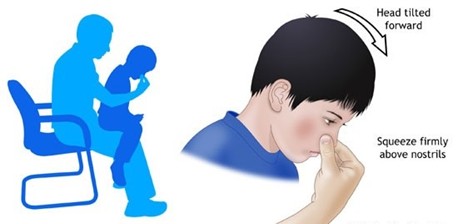

Os sangramentos nasais normalmente são de pouco volume e de curta duração e medidas simples costumam ser suficientes para interromper o fluxo de sangue. No caso de algum evento de epistaxe deve-se permanecer na posição sentada e comprimir ambas as narinas com os dedos em forma de “pinça”, como demonstrado na imagem abaixo.

Intuitivamente temos a tendência de inclinar a cabeça para trás, porém, quando fazemos isso, o sangramento é direcionado para a garganta e podem ocorrer engasgos e ingesta desse volume. A posição correta após fazer a compressão das narinas com os dedos é inclinar a cabeça para a frente para que isso não ocorra. Pode-se chupar gelo ou algo gelado a fim de esfriar a cavidade oral que consequentemente ajuda na constrição dos vasos sanguíneos do nariz. Normalmente após alguns minutos fazendo essas medidas há uma cessação do sangramento.